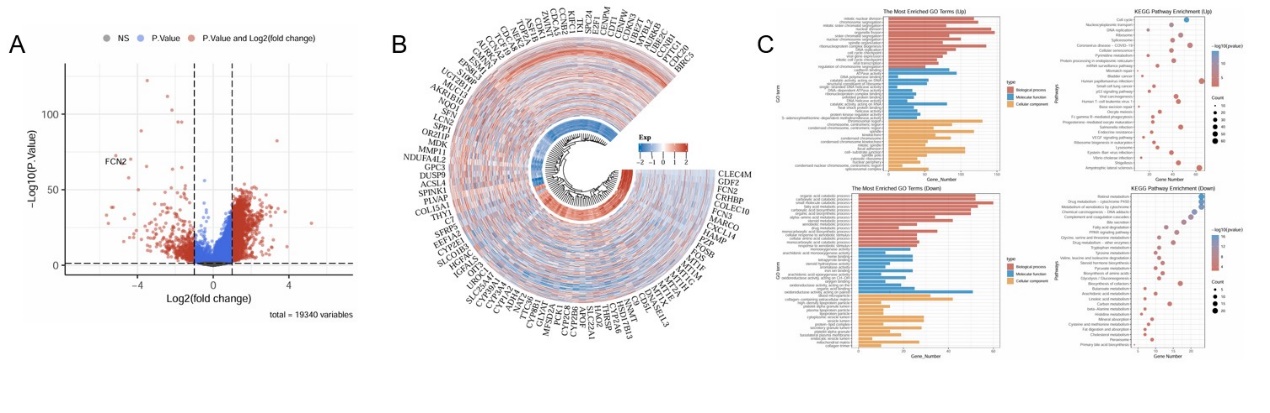

Further analysis of the GSE45267 dataset from the GEO database revealed 2,452 upregulated genes and 446 downregulated genes (Figure 2A). Notably, genes such as TTK, CENPW, NCAPG, BUB1B, KIF4A, and CCNB1 were upregulated in HCC, while IDO2, AOPF, NAT2, LPA, C3ORF85, BCO2, and C6 were downregulated (Figure 2B). Upregulated genes in the GEO dataset were predominantly involved in pathways such as mitotic nuclear division, chromosome segregation, the cell cycle, p53 signaling, DNA replication, and mismatch repair. Conversely, downregulated genes were enriched in pathways associated with complement and coagulation cascades, drug metabolism, chemical carcinogenesis, metabolism of xenobiotics, organic acid catabolic process, retinol metabolism, and fatty acid catabolism (Figure 2C).